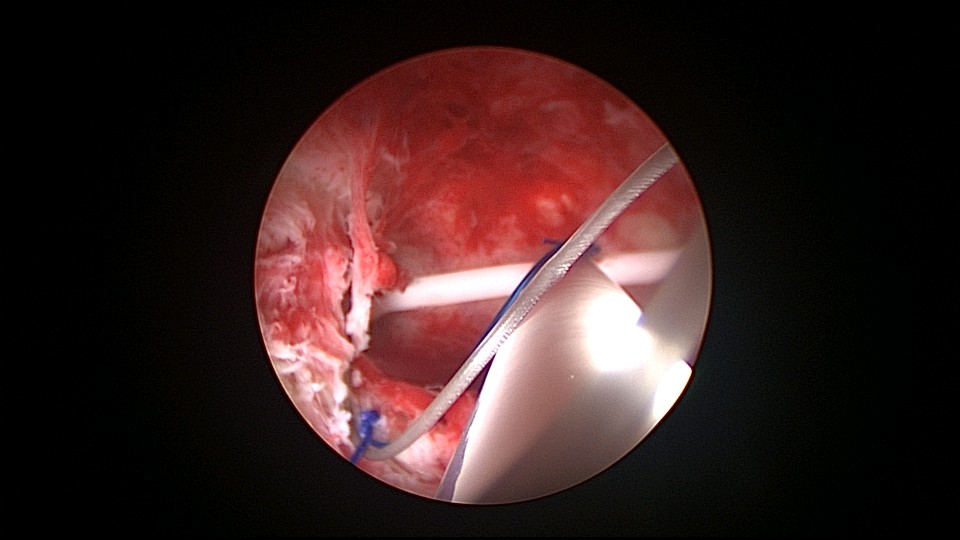

患者38岁,G2P1,剖宫产1次。安环13年,发现内膜息肉3年伴月经淋漓不净。2025年3月行宫腔镜取环、息肉切除,同时放置曼月乐环并固定。子宫后位,宫深7.5cm,宫型环位置正常,宫颈管及宫腔后壁见息肉,顺利取出节育环,切除息肉送病检,4-0不可吸收线将曼月乐缝合固定于宫腔上段后壁,第一次做宫腔镜下缝合固定节育环,体外打结后推结到位比较困难,今后改进缝合固定方式。病检为子宫内膜息肉及增殖期子宫内膜。2025年4月复查B超,曼月乐位置正常,环顶端距宫底1.3cm。